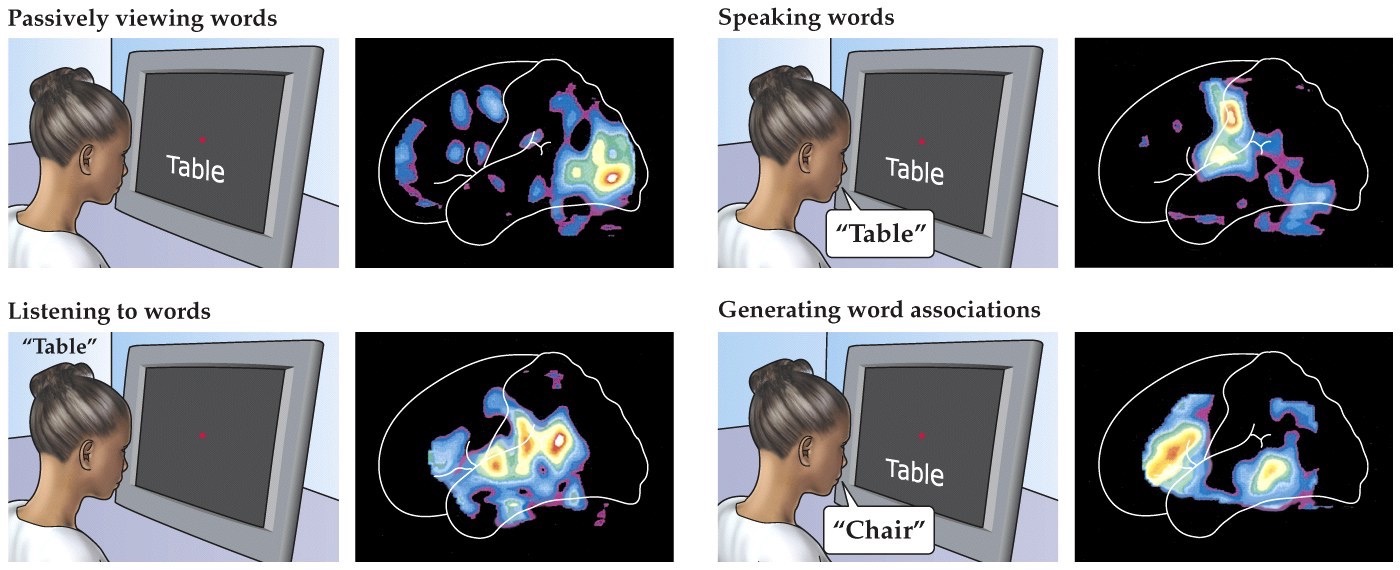

Mapping brain activity with human neuroimaging

Note:

- functional magnetic resonance imaging

- different patterns of brain activity localization depending on what the task is

- Actually sitting inside a small space magnet